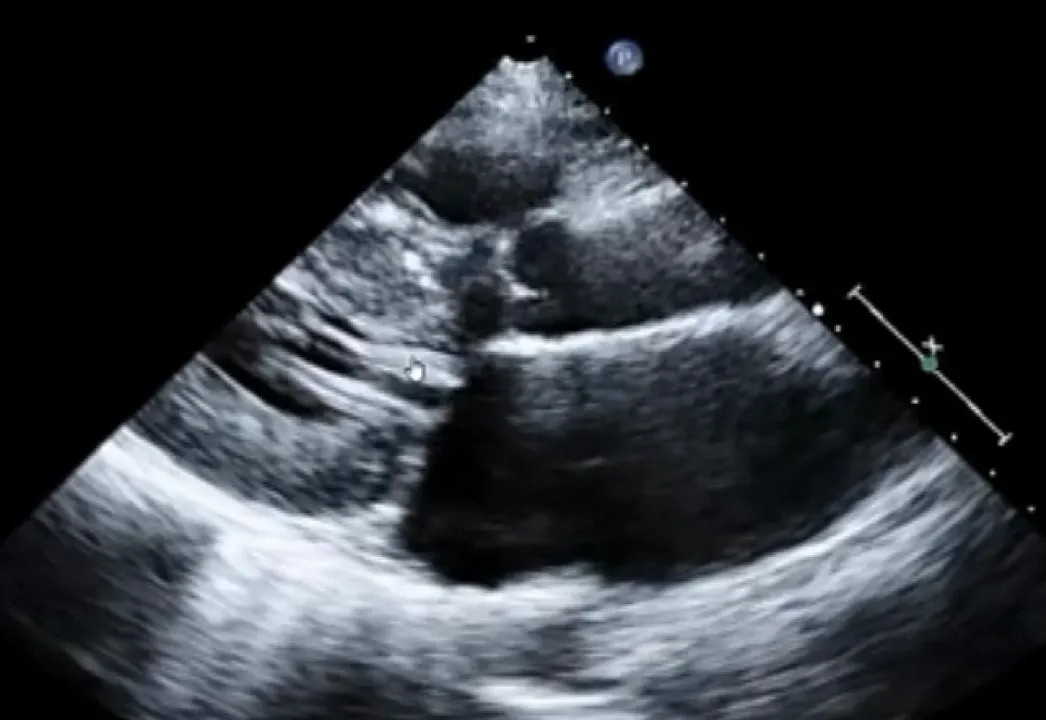

Asymmetric LV hypertrophy

Hyperdynamic LV

원인을 설명할 수 없는 심근의 비대 15mm이상

좌심실중격/후벽의 두께비율 1:3